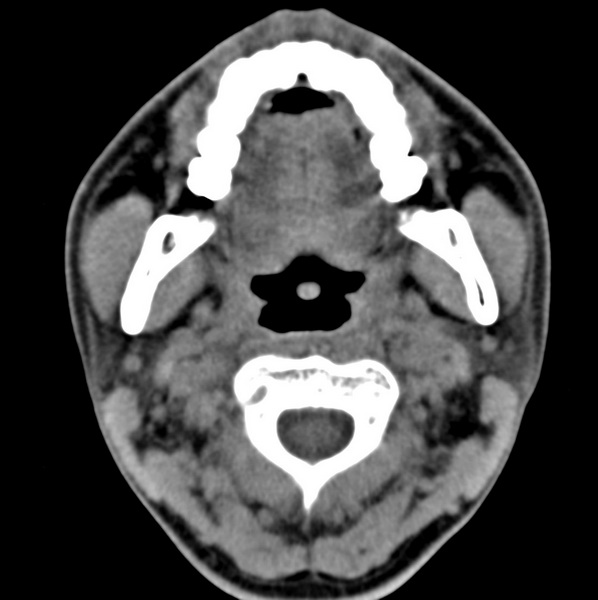

男、31、鼻咽部肿瘤放疗后请帮忙看看。

效果好,右侧破裂孔扩大,局部骨质缺损,为颅底骨质破坏。

1)鼻咽部肿瘤侵犯颅底放疗术后改变。2)左侧蝶窦炎。

咽后壁增厚,左侧咽鼓管隆突增大、咽鼓管咽口变浅,同侧咽旁间隙较窄。右侧颅底骨质破坏?为什么不在同一侧?

鼻咽部肿瘤侵犯颅底放疗术后改变.